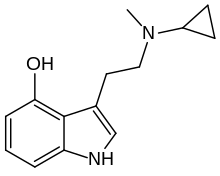

| McPT | artificial | H | CH3 | C3H5 | N-Methyl-N-cyclopropyltryptamine | 1373918-63-8 |